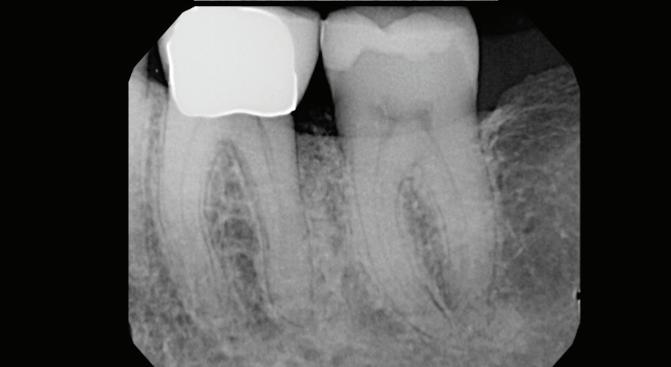

-year follow-up radiographs showed evidence of bone fill. Clinically, maturation of interdental tissue is evident as well.

-year follow-up radiographs showed evidence of bone fill. Clinically, maturation of interdental tissue is evident as well

Stability of the bone radiographically is evident as well.

-year follow up clinical photos are demonstrating stability of bone, lack of facial and minimal interproximal recession. Stability of the bone radiographically is evident as well.